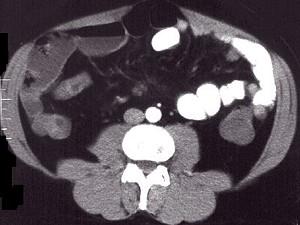

问题 女,30岁,右下腹痛,腹泻便秘交替出现,消瘦乏力,血沉加快,X线检查如图,最佳的诊断是 ( )

选项 A、结肠癌 B、阑尾炎 C、小肠结核 D、小肠克罗恩病 E、小肠癌

答案 D